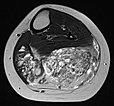

In der axialen T2-gewichteten MRT des linken Unterschenkels finden sich mehrere dilatierte, dysplastische Venen im Sinne einer venösen Malformation in der gesamten oberflächlichen Flexorenmuskulatur. Durch den niedrigen Durchfluss kommt es zur Stase des Blutes innerhalb der Malformation mit der Bildung von Flüssigkeits-Spiegeln. Praktisch der gesamte Muskel ist von Malformation und Fettgewebe durchsetzt. Großer Thrombus in einer dilatierten, dysplastischen Vene.

Auch in der axialen Kontroll-MRT in T2-Wichtung sind die Gefäßkanäle zum großen Teil verschlossen. Nach erfolgreichem Verschluss bleibt aber ein schwarz-weißes „Salz-und-Pfeffer-Muster“ bestehen, das typisch für eine FAVA ist. Es besteht aus Fettgewebe (hyperintens) und Bindegewebe (hypointens).